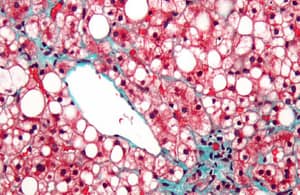

Dadas las manifestaciones multisistémicas (articular, renal y hepático) se sospechó una condición autoinmune, particularmente un debut de Lupus Eritematoso Sistémico (LES), obteniéndose anticuerpos antinucleares (ANA) positivos en 1/160, patrón moteado, pero con Anti-DNA negativo y complemento C3 y C4 normales. Todo ello motivó el estudio de autoinmunidad hepática, destacando la presencia de anticuerpos anti músculo liso (ASMA) positivos e IgG elevada, lo que orientó el diagnóstico hacia una Hepatitis Autoinmune (HAI), que fue confirmada por una biopsia hepática con lesiones características (Figura 1 fila superior). Inició entonces terapia esteroidal oral y azatioprina 100 mg/día logrando normalización de las alteraciones hepáticas y ausencia de sintomatología en tres semanas. Sin embargo, la proteinuria persistió por los siguientes 6 meses, en valores de 1 g/24 h, sin hematuria ni deterioro funcional, realizándose biopsia renal que mostró una Glomeruloesclerosis Focal y Segmentaria variedad NOS (“not otherwise specified”, sin alteraciones específicas ó clásica), con fusión pedicelar completa, ausencia de depósitos inmunes en la inmunofluorescencia y microscopía electrónica y compromiso túbulo-intersticial crónico, discreto y focal (Figura 1, fila inferior). La adición de terapia antiproteinúrica inespecífica (lisinopril oral a 10 mg/día) indujo rápida normalización a 0,2 g/24 h y tras 30 meses se mantiene con mínima dosis de prednisona, 100 mg de azatioprina e igual dosis de lisinopril, sin evidencia de actividad de sus patologías.

Figura 1. Lesiones histológicas. Fila superior (hígado) mostrando (a) infiltrado inflamatorio mononuclear con actividad de interfase (disrupción de la placa limitante); (b) balonización de los hepatocitos (flechas); (c) identificación de plasmocitos de localización periportal (reactividad de membrana celulares en inmunohistoquímica CD 138) y (d) escasa fibrosis (fibras colágenas en rojo) en la tinción de Van Gieson. Fila inferior (riñón): e) microscopía óptica en tinción de ácido peryódico de Schiff (PAS) mostrando la lesión de esclerosis glomerular focal (glomérulo destacado en círculo); (f) y (g) inmunofluorescencia glomerular negativa para C1q e IgG, respectivamente. En (h) microscopía electrónica con plegamiento de la membrana basal glomerular, ausencia de depósitos inmunes y desaparición completa de los pedicelos.